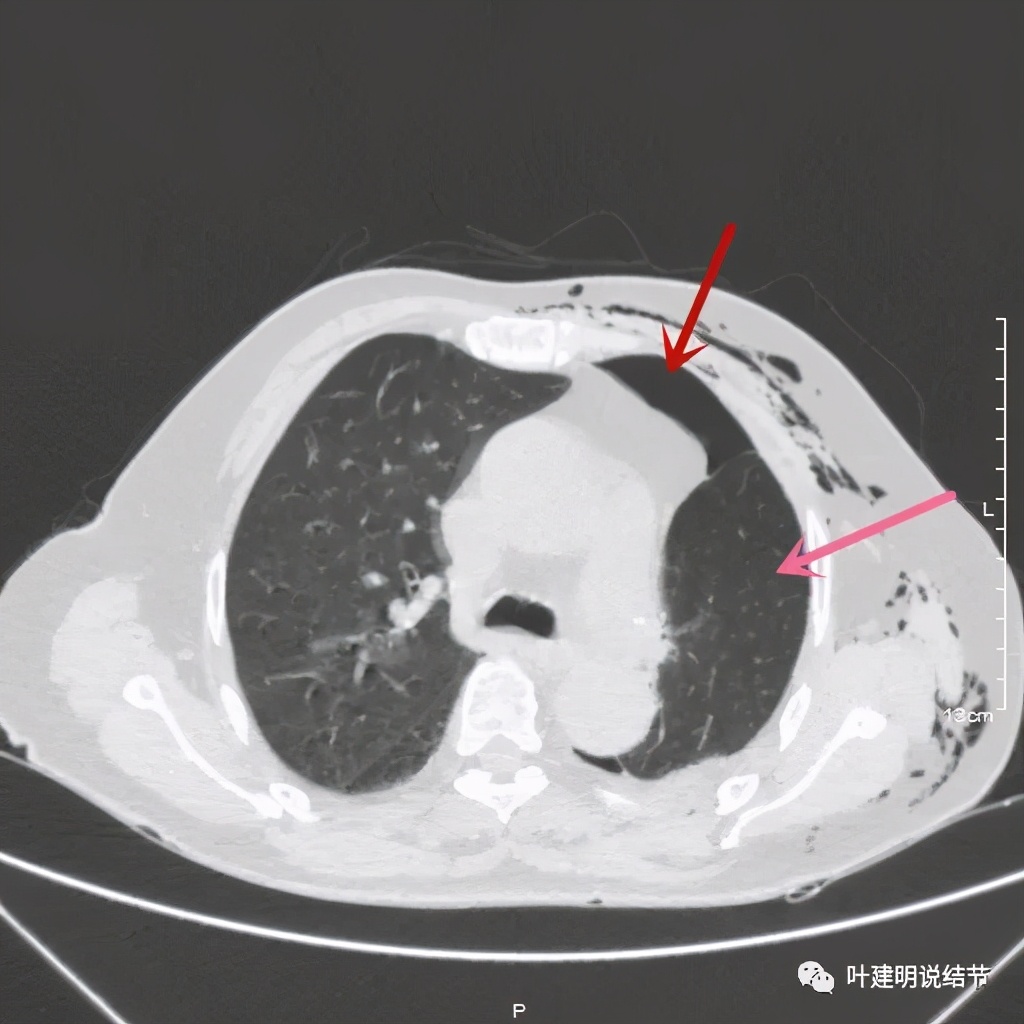

术后第二天患者乏力纳差,起不了床!而且CRP也大于100,我们的神经又紧张起来,怕支气管胸膜瘘,怕感染、怕有并发症发生。还好化验后是低钾,予以补充钾与镁2天后胃纳与精神均有明显改善,我们再加用静脉高营养支持治疗,补充白蛋白,情况逐渐好转。我们也于术后第4天查了CT,发现如下:

下叶膨胀良好

下叶膨胀良好,上叶残腔不大

下叶膨胀良好,上叶残腔不大,蓝色箭头示左主支气管

下叶膨胀良好,上叶残腔不大。桔色箭头示吻合口处,通畅

以上图像示下叶膨胀良好,上叶残腔不大,紫色箭头示吻合口以远的支气管通畅,肺膨胀佳